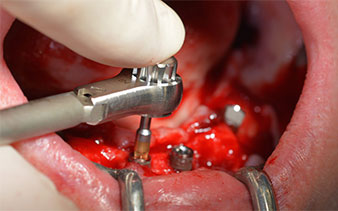

contra-ángulo de W&H

Fig. 12

32 Ncm

Fig. 13

El requisito imprescindible para el tratamiento inmediato es una alta estabilidad primaria. Para satisfacer dicho requisito, en este caso, se prescindió del corte de rosca. La unidad de accionamiento Implantmed de W&H empleada aquí, posee un modo propio para ello que también puede seleccionarse directamente y resulta imprescindible para muchas indicaciones. Los últimos giros para la inserción del implante superaron el valor de 32 Ncm, por lo que se realizaron manualmente. En tales casos, se recomienda utilizar la función autocortante de los implantes y girar el implante varias veces hacia delante y hacia atrás de forma que el implante se aproxime gradualmente hasta su posición definitiva sin ejercer una presión excesiva sobre el hueso (fig. 14).